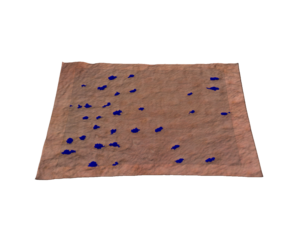

In 2D, this involves color analysis, followed by shape identification to eliminate other objects and retain only the pores. The results are images processed in black and white. You also get a spreadsheet with the median area, median diameter and pore density of each image.

3D analysis provides an additional dimension of pore depth. The 3D approach improves the sensitivity of pore detection. It can then be used to assess the depth of the pores and their possible filling.

Source image Processed image